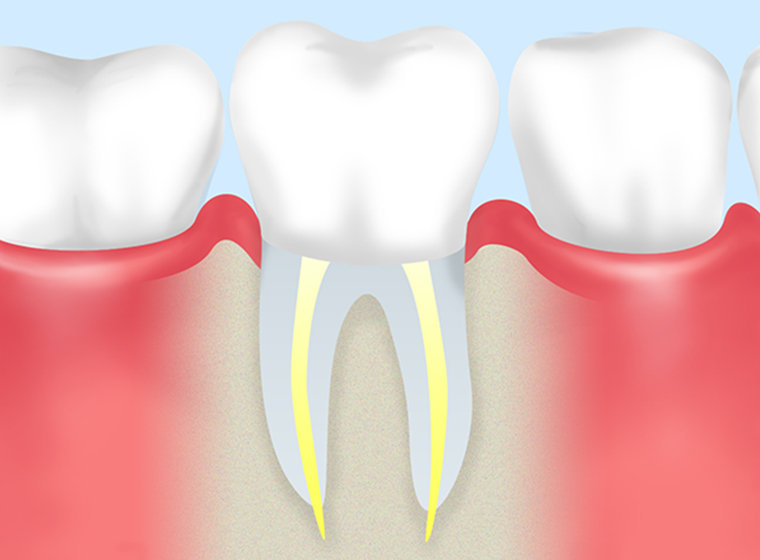

- STEP6

被せ物装着 -